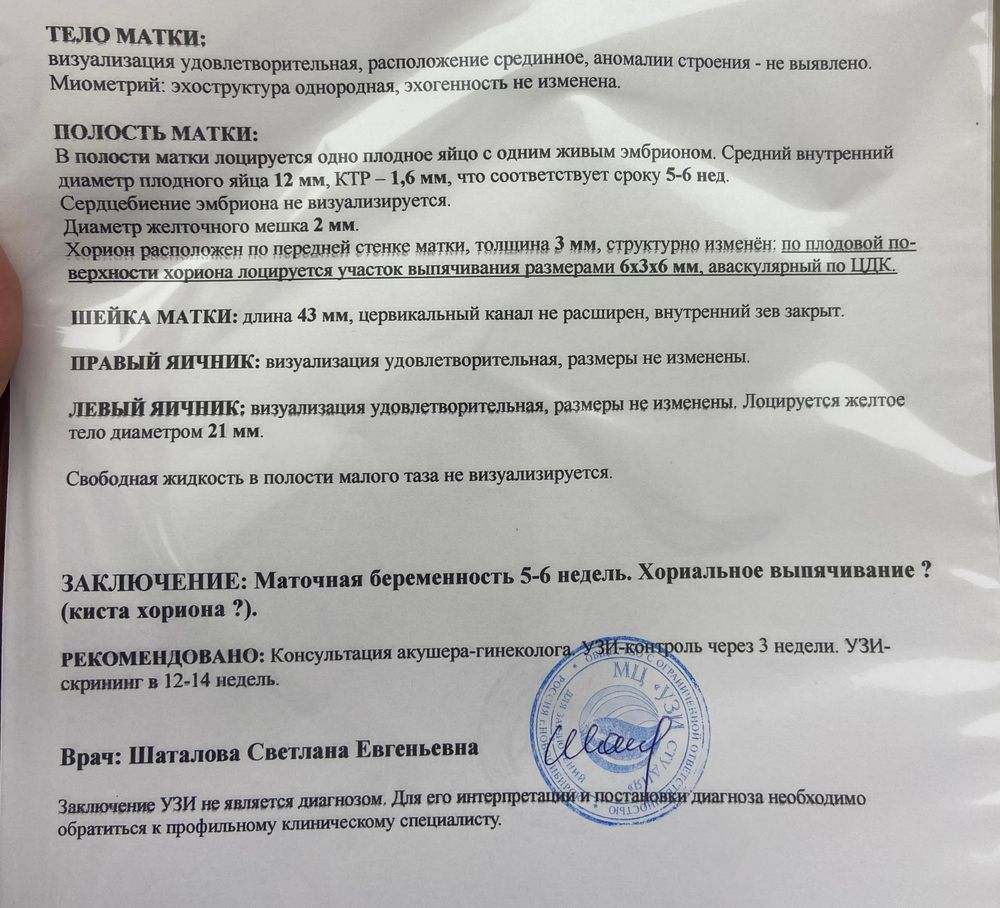

Добрый день. У кого было такое на 6 неделе? На узи увидели что-то. Либо сосудисто нервный пучок либо хориональное выпячивание. Гинеколог сказала возможно такое из-за воспаления в мазке. И мажущие выделения тоже может быть из-за этого. Выписали лекарства и контроль через 2 недели. У кого такое было?